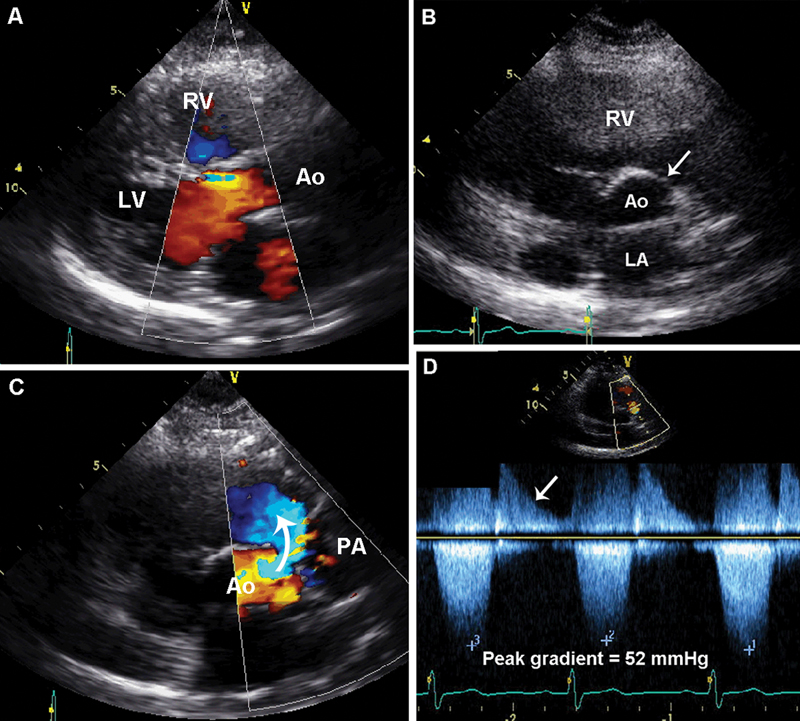

فحوصات تشخيصية لبعض امراض القلب والشرايين التاجية